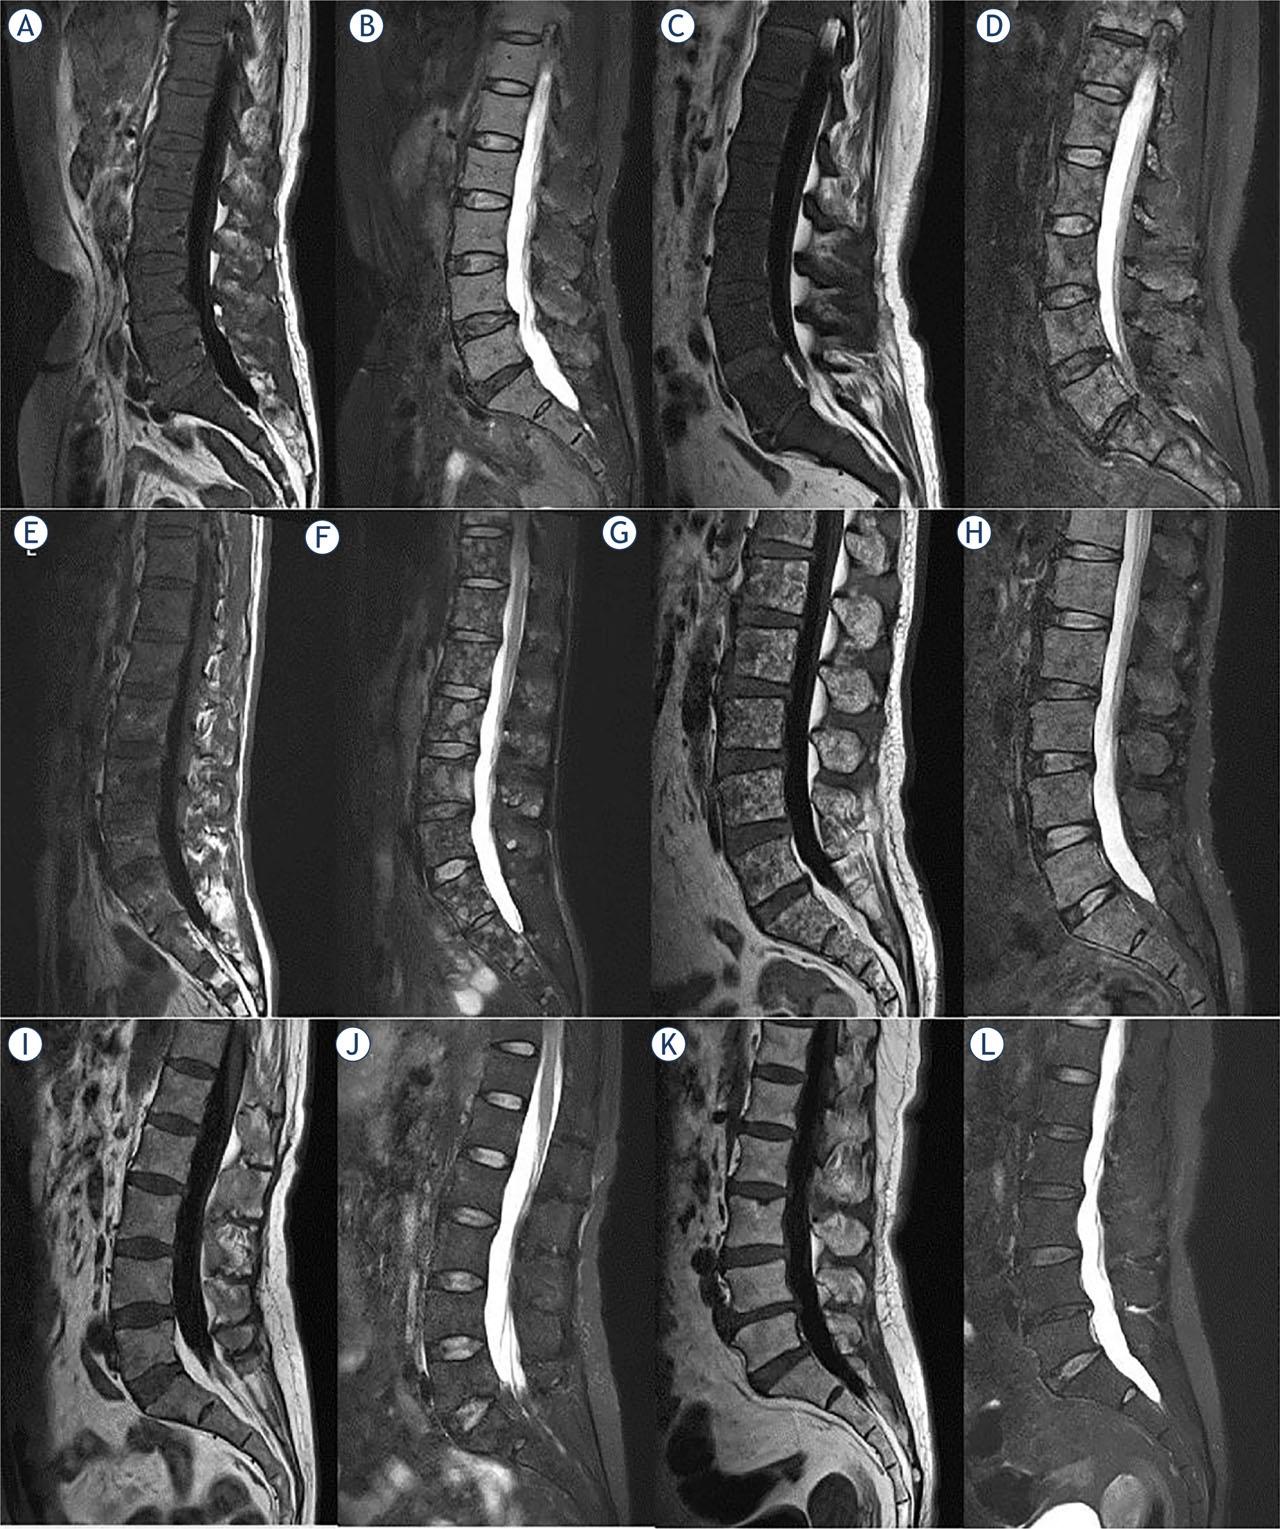

FIGURE 1.

FIGURE 2.

FIGURE 3.

FIGURE 4.

FIGURE 5.